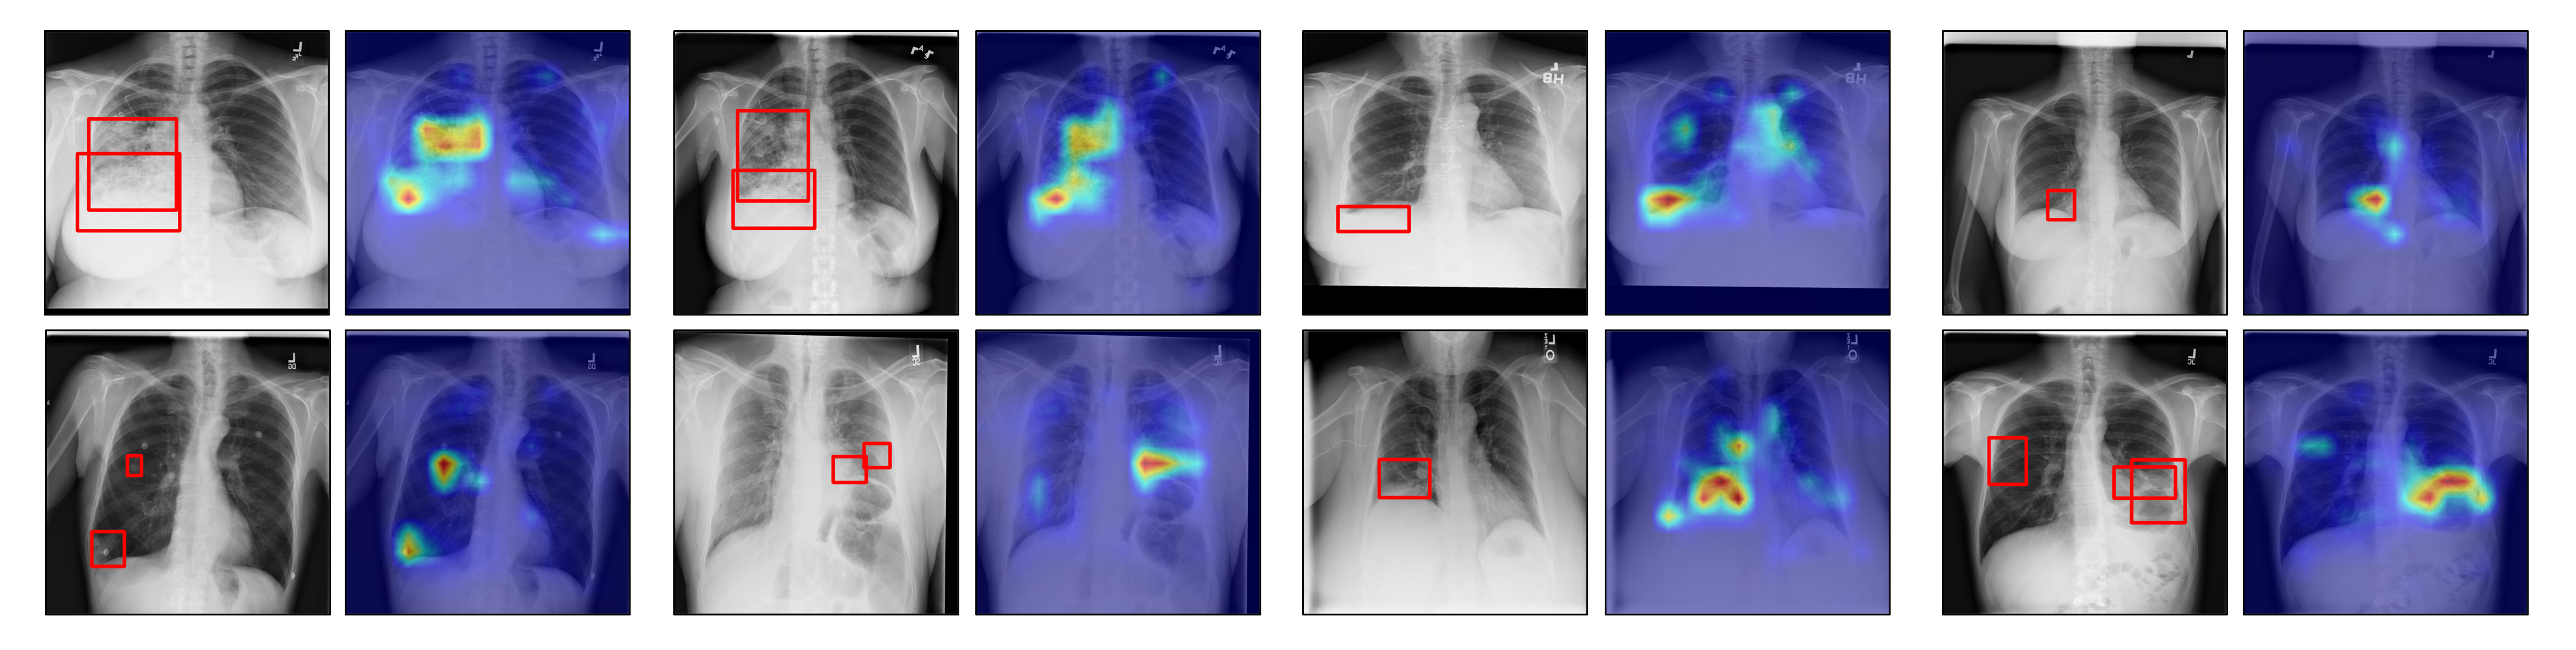

4.5.3 Qualitative grounding visualization

In Fig. 7, we present several examples of lesion grounding on ChestX-Det10 by UniChest. To provide an intuitive visualization, we generate spectrum heatmaps on the original CXR images based on the MoE-QN Module’s regional cross-attention maps in transformer decoder layers. By comparing the model-detected lesions with the bounding boxes annotated by expert clinicians, we observe a strong alignment between model findings and the diagnoses made by experts, demonstrating the reasoning ability and interpretability of UniChest.